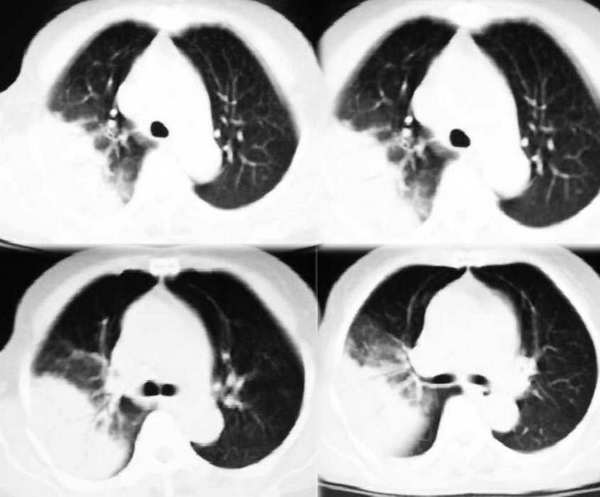

右肺大片状阴影,边缘模糊,其内见充气支气管征。肺门结构正常。支持肺炎性病变。

右肺上叶尖后段大片扇形实变影,密度较均匀,内见支气管空气造影征,气管腔静脉间淋巴结稍大呈小结节影,结合临床考虑大叶性肺炎。

右肺大片云片状渗出性阴影,边缘模糊,扇形分布其内见充气支气管征,肺纵比率<50%,结合病史支持大叶性肺炎诊断。

右上叶后段见大片状实变阴影,见含气支气管征,近肺门见支气管血管束增粗,上腔静脉后见小淋巴结. 后胸膜腔见少量积液. 印象:1,大叶性肺炎.2,节段性肺炎<混合菌感染>.3.建议抗炎后复查待除外其他病变

右肺上叶肺实变,内见①支气管气像②边缘模糊③叶间裂稍饱满这些都是支持肺炎的证据。尤其是边缘模糊,其病理学依据是炎症渗出性物质通过肺泡间孔和/或呼吸性细支气管向临近的肺组织蔓延渗透,和其他表现在一起成为诊断肺炎的重要表现。